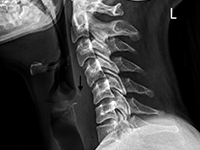

We present a case of a 33-year old woman, who swallowed a piece of glass. Endoscopic evaluations did not reveal the foreign body. Radiography of the neck showed a foreign body on the level of the upper oesophagus sphincter and computed tomography confirmed its presence in the soft tissues of the neck, 8 mm away from common carotid artery. The glass splinter was removed by the open surgery.

Foreign bodies carry a risk of penetrating the wall of the digestive tract and migrating into the soft tissues. Plain film radiography detects a radiopaque foreign body and computed tomography provides its accurate localization.